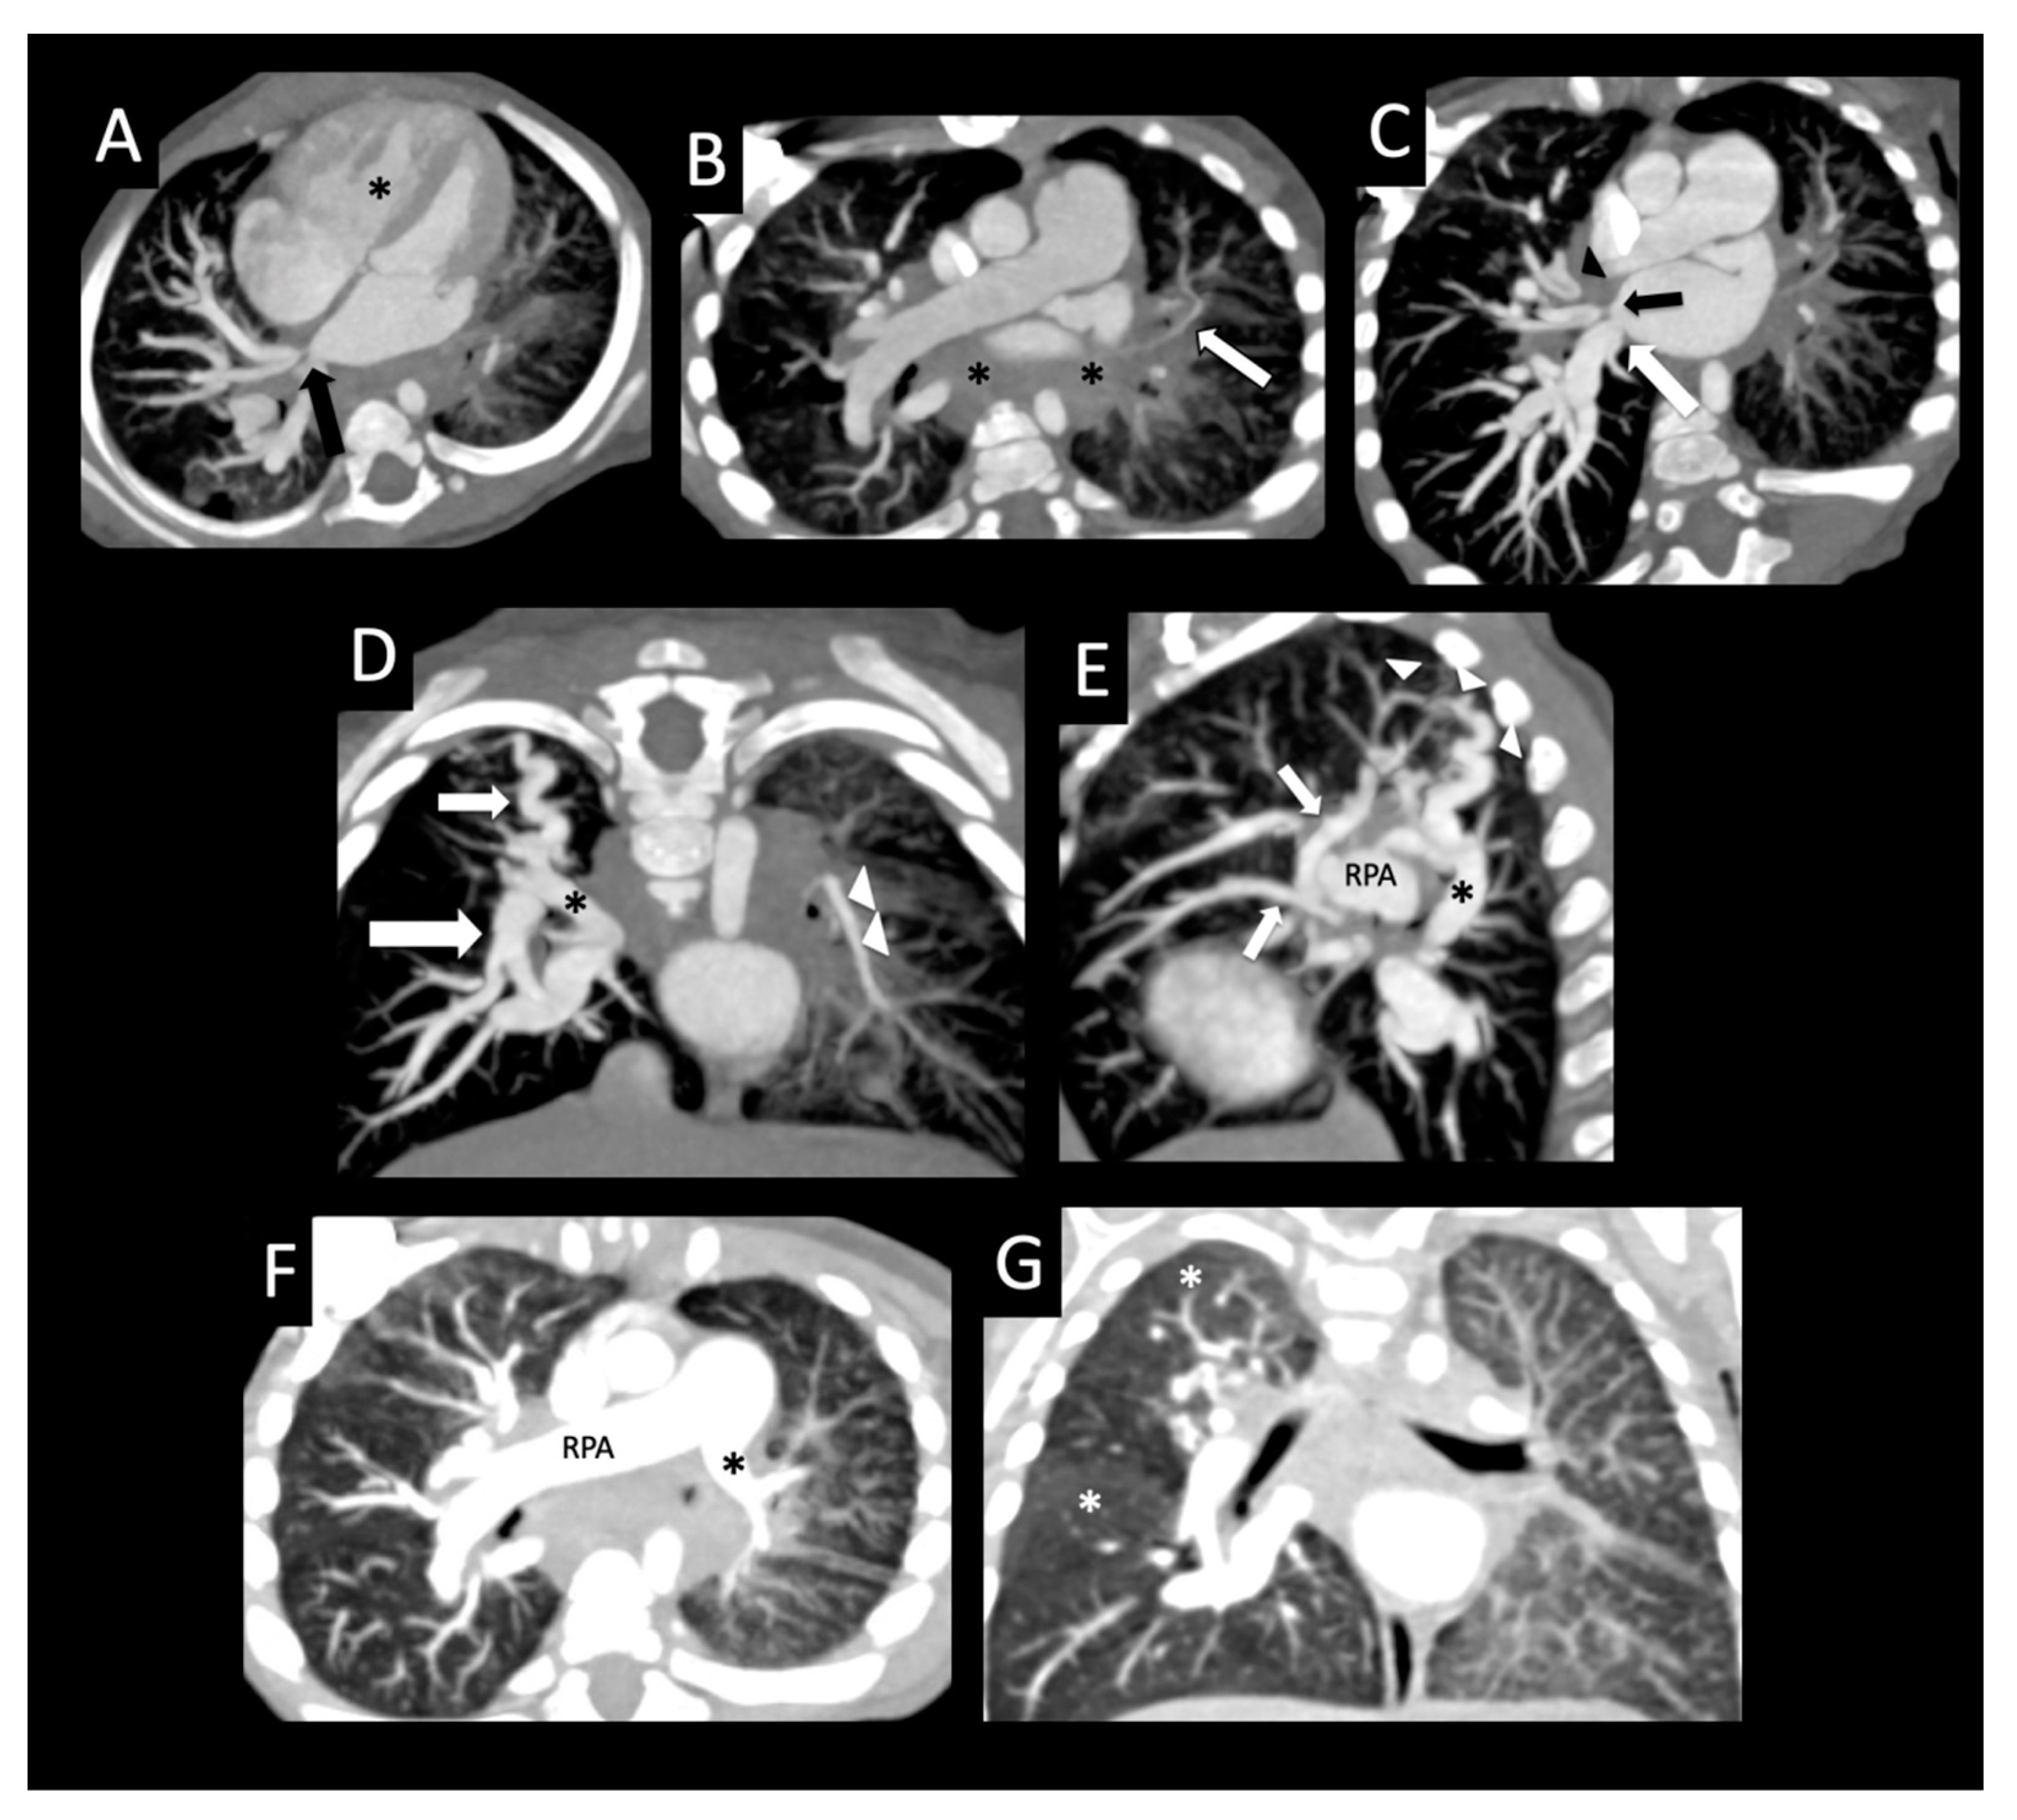

Figure 12. Pulmonary vein stenosis after repair of congenital heart disease. Full-term infant who developed severe bilateral pulmonary vein stenosis after surgical repair of subaortic stenosis, coarctation of the aorta, and ventricular septal defect. The right common pulmonary vein ostium was resected, and the left common confluence was anastomosed to the left atrial appendage with subsequent recurrent left pulmonary vein stenosis and stenting of the left upper pulmonary vein. Follow-up CT shows the left upper pulmonary vein stent (coronal image, (A)) extending to the lingular vein (large arrow) that crosses and “jails” the left upper pulmonary vein branches (arrowheads), and mild right upper pulmonary vein ostial stenosis (small arrow, (A)). Axial image (B) shows moderate stenosis of the right lower pulmonary vein ostium (arrow) and left-sided perihilar induration (arrowheads). The left lower pulmonary vein could not be visualized, consistent with atresia. Axial image (C) shows diffuse wall thickening of the posterior left atrium (arrows). The right pulmonary artery (RPA) is dilated relative to the left pulmonary artery (*) (axial image, (D)). Coronal (E) and sagittal (F) images show diffuse decreased vascularity of the left lung relative to the right, and peripheral cysts within the superior segment of the left lower lobe (arrows).

We identified a high lung severity score as a univariate predictor of death. Children with PVS have multiple findings that contribute to the lung severity score, including interlobular septal thickening, ground glass opacity, lung segment and pulmonary artery hypoplasia, pleural thickening, mediastinal and perihilar induration, and cysts. Interlobular septal thickening and ground glass opacity were seen in the majority of patients, and are consistent with interstitial pulmonary edema from chronic pulmonary venous hypertension. Diffuse pleural thickening tends to be seen around lobes or entire lungs involved with more severe PVS (Figure 11). Lobar or total lung abnormalities associated with severe PVS with atresia included diffusely small size of the affected lobe or lung together with decreased size of the feeding pulmonary artery and decreased vascularization (Figure 12). Segmental lung or pulmonary artery hypoplasia could be attributed to decreased growth of the lung due to chronic hypoperfusion.

Central intraparenchymal and peripheral lung cysts were found in patients with severe PVS with atresia (Figure 10 and Figure 12), reflecting severe lung damage and fibrosis. Similar to other pulmonary findings in PVS, cysts are also nonspecific and can be seen in other forms of pulmonary disease such as chronic lung disease (Figure 8 and Figure 9), pulmonary interstitial glycogenosis, primary surfactant deficiency disorders in term infants, and certain genetic conditions such as Trisomy 21 [20,21]. Therefore, the distribution of lung cysts and knowledge of any underlying confounding conditions must be considered before lung cysts can be attributed to lung damage associated with PVS.